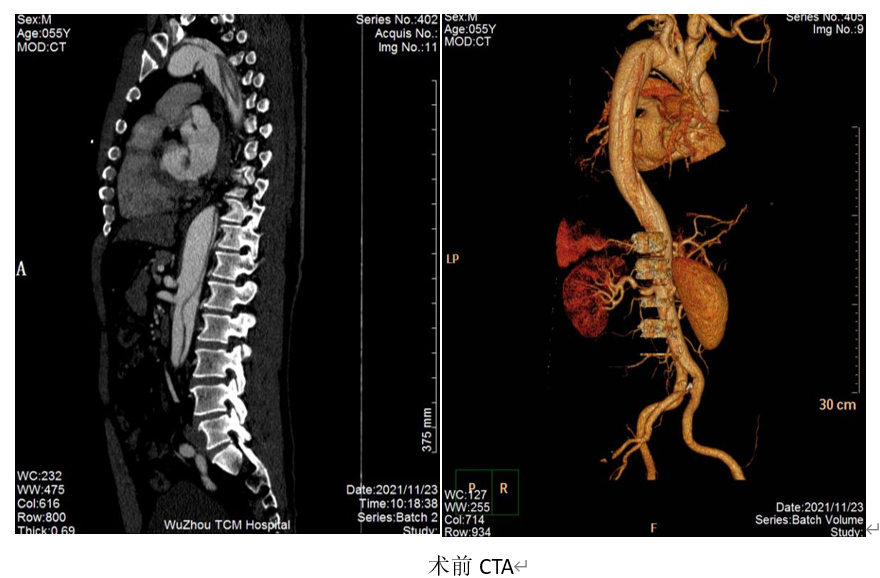

近期,刘某因运动后出现胸痛来我院就诊,急查CTA检查结果显示:主动脉夹层DeBakeyⅢB型。收住我院血管介入科,入院后予降血压、降心率及止痛对症治疗,因病情危重,后转入重症医学科。在住院完善检查同时,我院血管介入科主任、副主任医师陈庆航、傅建斌副主任医师、郭文震主治医师经过全面、慎密的评估与讨论,决定对患者施行主动脉造影及主动脉覆膜支架腔内隔绝术,手术安排在入院后第二天晚上,经过4个小时的手术,成功置入主动脉覆膜支架。